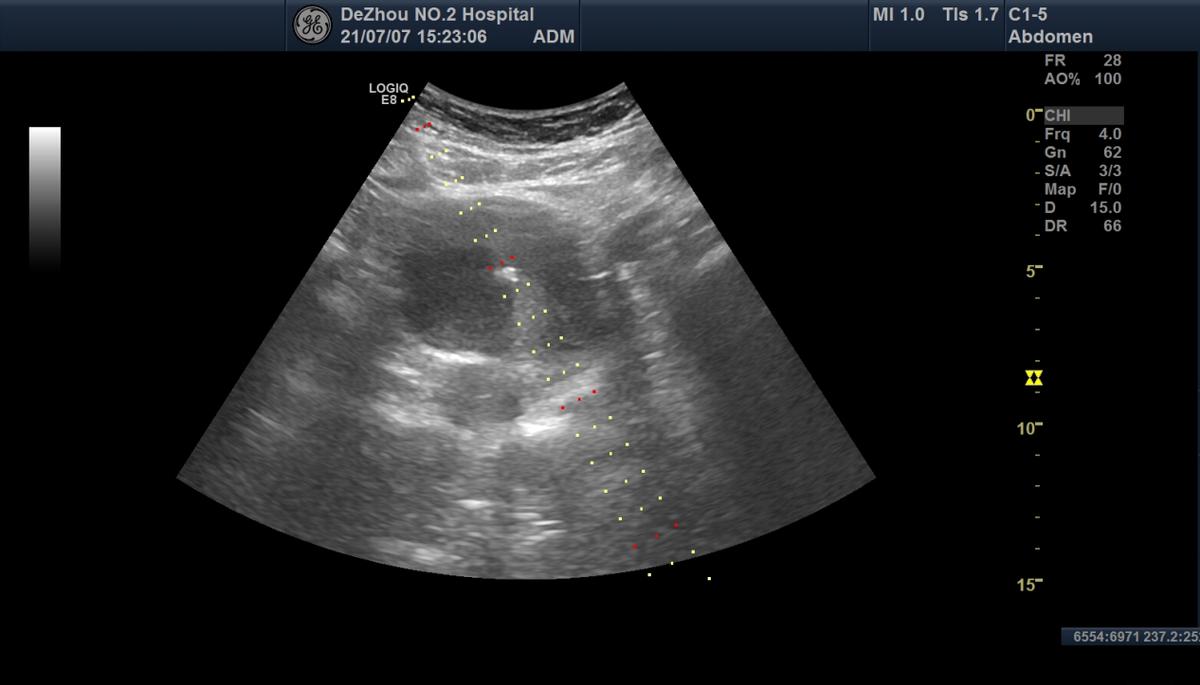

抽吸囊液

冲洗囊腔